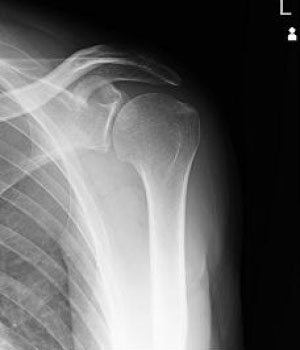

エックス線を利用して検査をするいわゆる“レントゲン撮影”です。

胸部、腹部、全身の骨の撮影を行います。心臓の大きさや肺の異常陰影、ガスの状態や骨の形、骨折の有無、関節の状態などがわかります。

当院ではフラットパネル(FPD)というシステムを導入し従来よりもエックス線の感度が高く低被ばくで撮影ができるようになりました。撮影効率も向上し撮影待ち時間も短縮しています。